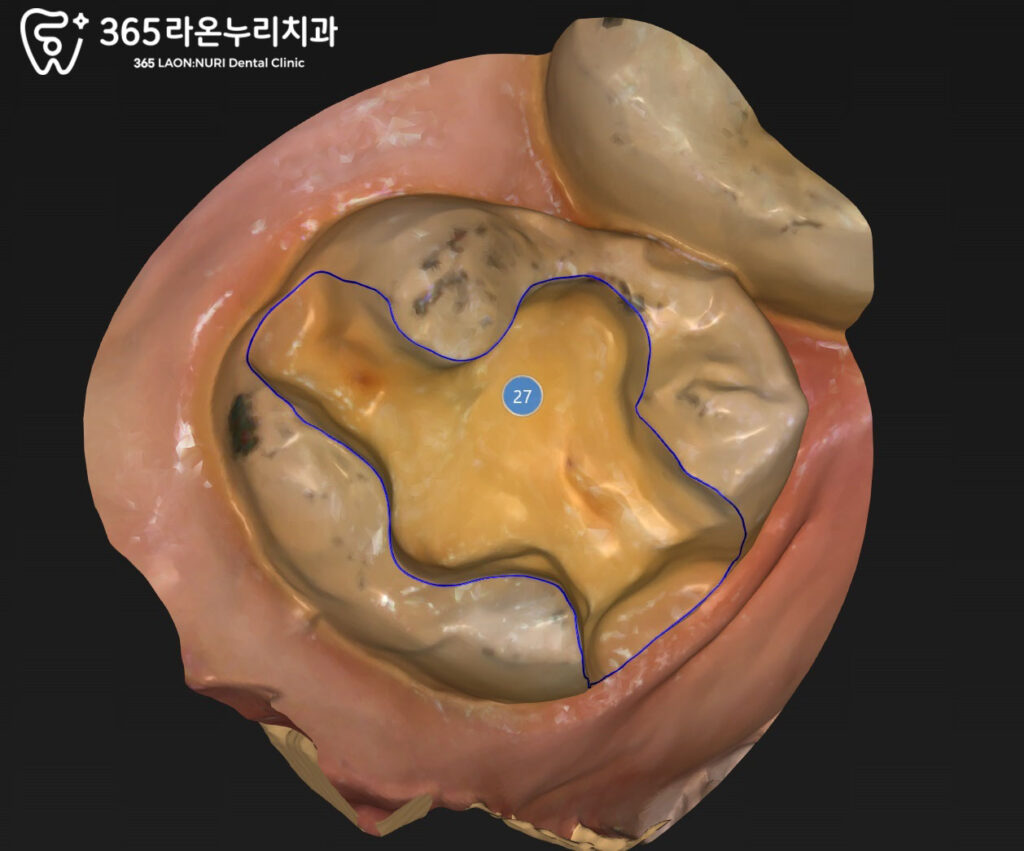

인레이 prep 도중 파절선 발견

인레이 수복을 하기 위해

치아를 삭제하는 과정에서

예상치 못하게 파절선이

발견되는 경우가 있습니다.

내부에서는 이미 치아가 약해져

균열이 진행된 상태였던 것이죠.

이러한 파절은 시간이 지나면서

더 큰 파절로 이어질 수 있고,

경우에 따라 인레이 대신

크라운으로 치료 계획을

변경해야 될 수도 있습니다.

그러나 오늘 신장동 치과 에서

준비한 케이스는 resin base를

밑에 깔아 보강한 후

인레이로 수복할 수 있었습니다.

인레이 보철 제작 과정

우식이 인접면까지 퍼져 있는 경우에는

보철 치료 시 정밀한 적합도가

특히 중요합니다.

이때는 구강 스캐너를 이용해

치아의 형태와 주변 관계를

더욱 정확하게 확인해

환자분의 치아에 딱 맞는

보철물을 제작할 수 있으며

결과적으로 음식이 잘 끼지 않고

오래 사용할 수 있게 됩니다.